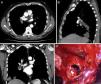

TAC torácico que demuestra la presencia de imágenes nodulares hipodensas en el interior de la arteria pulmonar derecha, sugerentes de quistes en cortes axial, sagital y coronal (A-C). Hallazgos operatorios tras clampaje de arteria pulmonar derecha y arteriotomía de la rama lobar inferior, en cuyo interior se evidencian membranas hidatídicas (D).

Se trata de un paciente de 56 años sin hábitos tóxicos ni antecedentes médicos de interés que acudió a su médico de atención primaria por expectoración hemoptoica de 2 semanas de evolución acompañada de dolor torácico derecho. En la radiografía de tórax se objetivó una masa polilobulada en lóbulo inferior derecho con engrosamiento hiliar, que sugería neoplasia pulmonar como primera posibilidad. La TAC torácica evidenció una masa de 11×8,8cm en lóbulo inferior derecho con áreas hipodensas en su interior sugerentes de quistes. La masa contactaba con la superficie pleural en una extensión de 10cm y se extendía con distribución peribroncovascular hacia la región hiliar, presentando múltiples imágenes nodulares de similares características y de hasta 4,5cm a nivel intra-arterial. Los hallazgos radiológicos eran sugerentes de hidatidosis pulmonar con invasión de la arteria lobar inferior derecha (fig. 1A-C).

Se realizó la resección quirúrgica manteniendo el tratamiento antiparasitario durante todo el período perioperatorio. Los hallazgos intraoperatorios consistieron en hepatización del lóbulo inferior derecho, importante vascularización procedente de arterias bronquiales y aumento del calibre de la arteria lobar inferior derecha. Tras el control y clampaje de la arteria pulmonar derecha, en su origen extrapericárdico, se realizó una arteriotomía a nivel de la rama lobar inferior y la extracción de los quistes hidatídicos intravasculares (fig. 1D). La luz proximal de la arteria pulmonar fue aspirada hasta la altura del clampaje. Dada la importante reacción inflamatoria perihiliar, no fue posible disecar el bronquio intermediario proximal, por lo que se realizó bilobectomía media-inferior.